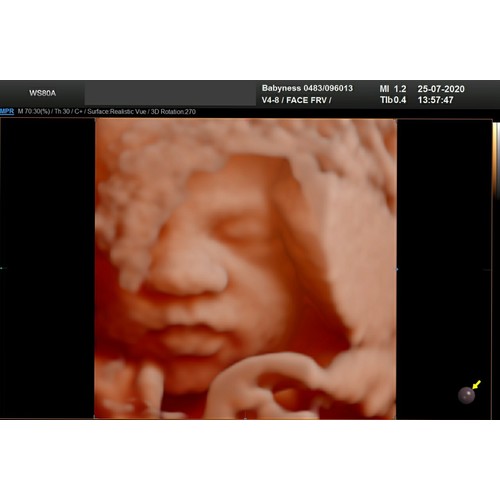

24.2

Onze dochter heeft bij elke echo dr handen voor dr gezichtje , dit was dus het beste resultaat..

Toch vind ik m prachtig! 😍 papa's indo neusje en mama's volle lippen 🥰